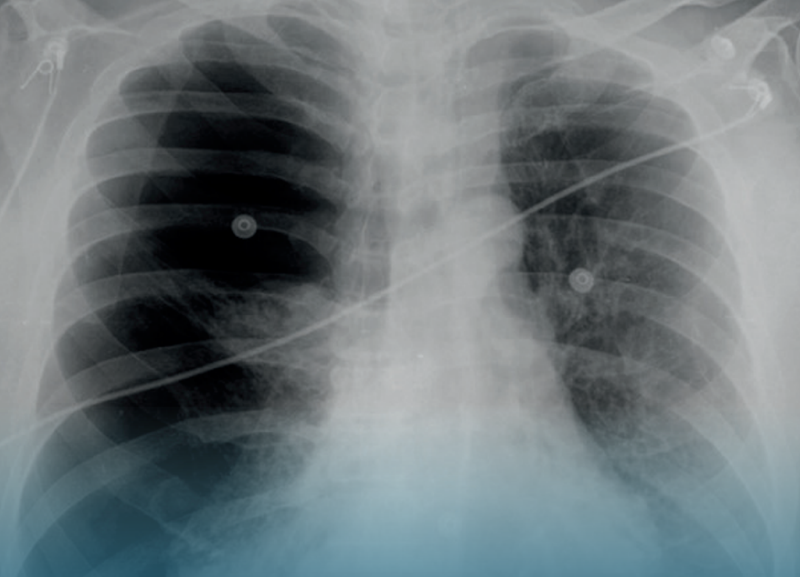

La EPOC se caracteriza por la inflamación crónica de los pulmones, lo que dificulta la respiración. Por ello, SSO exhorta a la población evitar la exposición a factores de riesgo como el tabaquismo, la contaminación ambiental, el polvo y sustancias químicas en espacios laborales.